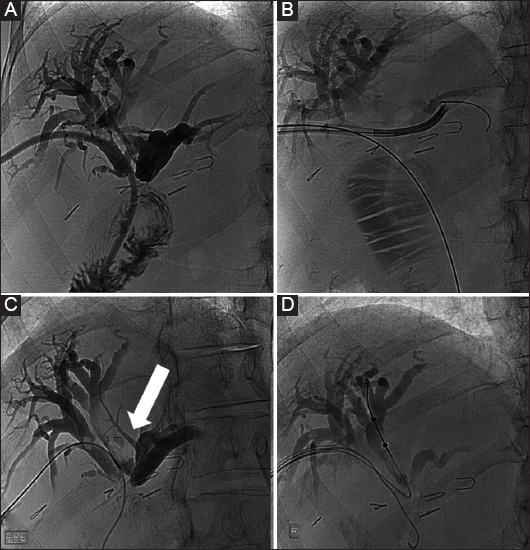

Figure 1 (A) Magnetic resonance cholangiopancreatography (MRCP), confirming the presence of biliary stones in a patient post biliodigestive anastomosis (BDS). Biliary duct dilation indicates the stenosis of the BDS as the underlying factor for stone formation. (B) Percutaneous transhepatic cholangiography and internal external drainage of the biliary system was performed as initial measure to prevent sepsis and to reduce further stone formation. (C) The patient returned 2 weeks later and most of the stones had been reabsorbed. The remainder were pushed via the BDS with a balloon catheter. Dilation of the stenosed BDS followed. (D) an external drainage catheter was left in situ for another 3 days in case hemobilia occurred post dilation. No stones are present in the biliary system

thumblarge

Figure 2 A 45-year-old female patient who developed benign biliary stenosis post laparoscopic cholecystectomy, with presence of stones. (A) Bilateral biliary drainage and dilation of the stenotic anastomosis with a high-pressure balloon (arrow). (B) Long-term drains with discoid end were left in situ for several months and the patient returned every 3 weeks for sequential dilation

Figure 3 A 48-year-old female patient with benign stenosis post biliodigestive anastomosis. (A) Initial drainage because of multiple small stones. (B) Cholangioscopic inspection to assess the presence of stones that were not visible in the cholangiogram. (C) Three months later, a new cholangiogram revealed the presence of a large stone (arrow). (D) The stone was retrieved with an extraction balloon. Presence of a “buddy-wire” to maintain access to the biliary tree

The success rates of balloon angioplasty for intrahepatic bile duct stone reach as high as 95.23% [11,41] of cases, with an average procedure duration of 65.8±5.3 min. On average, patients stayed in the hospital for 10.7±1.5 days. No instances of pancreatitis, gut issues, or perforations in the biliary duct were reported. Over a follow-up period of 2 years, there were no signs of reflux cholangitis or stone recurrence [11]. Comparing percutaneous transhepatic papillary balloon dilation (PTPBD) with ERCP, the PTPBD technique had a success rate of 99% compared to 98% for the ERCP technique (relative risk 1.02, 95%CI 0.91-1.08; P=0.12). Complication rates were lower for PTPBD at 4% (13 of 360) versus ERCP at 8% (13 out of 171) (relative risk 0.27, 95%CI 0.12-0.61; P<0.001). The PTPBD procedure took more time under fluoroscopy and resulted in greater radiation exposure, with an average difference of 28.7 min (95%CI 22.2-35.2) and 384.3 mGy (95%CI 296.5-472). When matched groups were compared using a propensity score analysis, PTPBD displayed a marginally better success rate and notably fewer complications [42] (Table 1).